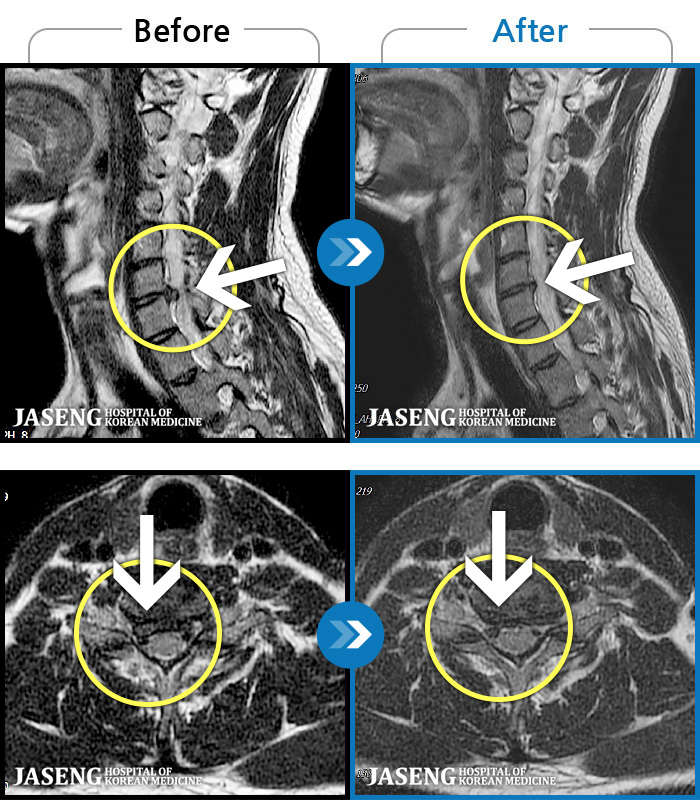

MRI ġ

1,301 MRI ũ ʸ Ȯϼ.